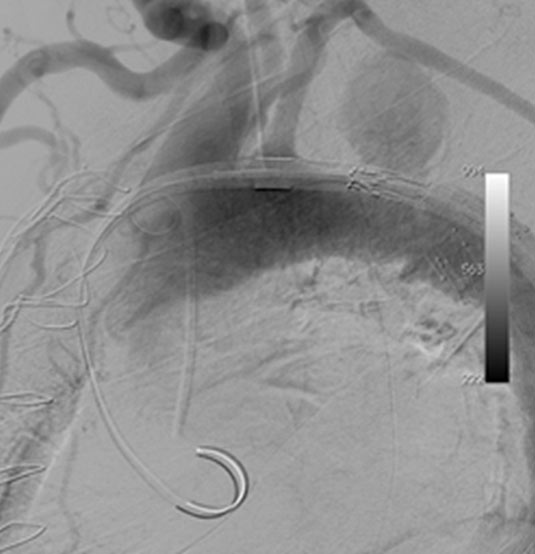

The patient underwent repeat CTA 1 month later which demonstrated thrombosis of the false lumen except for a 4.5 x 4.6cm pseudoaneurysm proximal to the distal repair. (Figure 4) Since the new finding appeared to have a defined neck, the possibility of an endovascular exclusion of the fenestration was discussed with the back-up plan being either open or hybrid arch replacement. The patient underwent a carotid subclavian bypass using an 8mm Gore-Tex ring graft (WL Gore & Associates Inc, Flagstaff, AR) to extend the proximal landing zone. Aortic coverage was planned from the combined origin of the brachiocephalic and left common carotid arteries (bovine arch anatomy) down into the previously placed tube graft. Two days later, two Cook TX2 thoracic endografts (Cook Inc, Bloomington, IN) 30 x 120mm and 36 x 127mm were overlapped to exclude the intimal defect. Completion angiography demonstrated contrast in the proximal subclavian without perfusion of the false lumen. (Figure 5)

Figure 5a. Intraoperative angiogram demonstrating 4.4 x 4.6cm pseudoaneurysm distal to the left subclavian artery.

Figure 5b. Angiography after carotid-subclavian bypass and exclusion of pseudoaneurysm with a Cook TX2 thoracic graft. Note bovine arch anatomy with combined origin of brachiocephalic and carotid arteries.